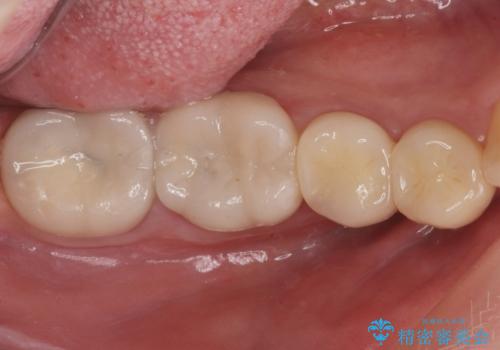

樹脂で継ぎ接ぎになった歯 セラミッククラウンでの治療

- 右下45:仮歯+ジルコニアクラウン/11,000円+110,000円費用は治療当時の料金となります

樹脂の材料と歯の境界部分は虫歯・着色の好発部位となります。

度重なる治療で継ぎ接ぎになってしまった場合はクラウンで歯を覆った方が虫歯・着色のリスクを減らすことができます。